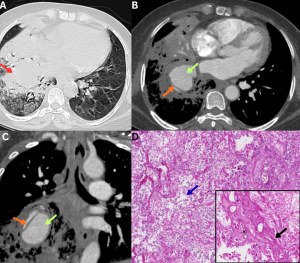

Fig 14: Case 1 -

Clinical history:

A 45-year-old patient with poorly controlled diabetes mellitus presented with fever, cough, and pleuritic chest pain.

Figure A:

Erect AP chest radiograph demonstrates multiple inhomogeneous air-space opacities in the bilateral lung fields (green arrows).

Figures B and C:

Coronal and axial HRCT images demonstrate multiple lesions with central ground-glass attenuation surrounded by a peripheral rim of consolidation in both lungs (red arrows), consistent with the reverse halo sign.

.......Case 2 -

A 50-year-old immunocompromised male presented with acute febrile illness and hemoptysis.

Figures D and E:

Axial and coronal HRCT images demonstrate multifocal areas of consolidation with surrounding peripheral ground-glass attenuation (orange arrows), representing the halo sign. Additional ill-defined ground-glass opacities are noted in the bilateral lung fields (blue arrows).